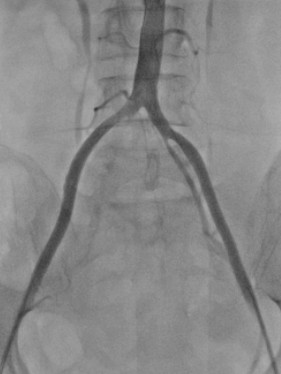

经过CTA证实,伊女士出现的是腹主动脉骑跨栓,从腹主动脉下段分叉开始都出现了不同程度的栓塞,双下肢出现了严重的缺血。

图中箭头所示:术前CTA提示腹主动脉双髂动脉骑跨栓,腹主动脉下段及双髂动脉血流中断

术中DSA:箭头提示双髂动脉血栓栓塞,血流中断

术中DSA:双髂动脉血流恢复